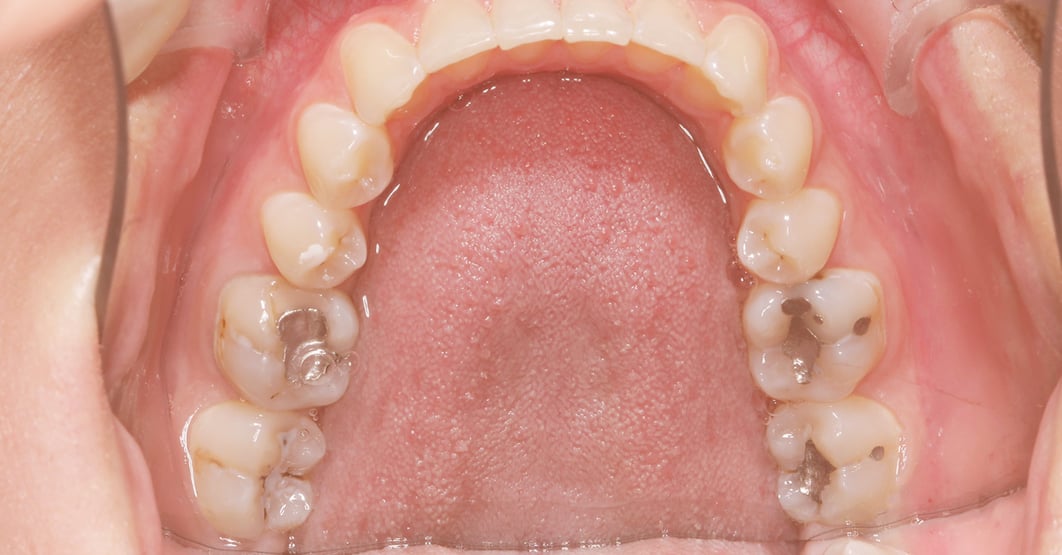

Why Replace Metal Fillings . amalgam fillings are the main source of inorganic mercury exposure (besides occupational exposure) for people with these kinds. Most often, it is the result of. There are several reasons why your filling may need to be replaced over time. understanding when and why to replace. can you replace silver fillings with white fillings? Over time, the seal connecting the. It is a relatively common procedure to replace amalgam fillings. why does my filling need to be replaced? what are amalgam dental fillings and why are they controversial? one of the primary reasons for replacing amalgam fillings is the development of new decay around the existing filling.

There are several reasons why your filling may need to be replaced over time. what are amalgam dental fillings and why are they controversial? one of the primary reasons for replacing amalgam fillings is the development of new decay around the existing filling. amalgam fillings are the main source of inorganic mercury exposure (besides occupational exposure) for people with these kinds. Over time, the seal connecting the. Most often, it is the result of. It is a relatively common procedure to replace amalgam fillings. understanding when and why to replace. why does my filling need to be replaced? can you replace silver fillings with white fillings?

Why Replace Metal Fillings Over time, the seal connecting the. why does my filling need to be replaced? Over time, the seal connecting the. what are amalgam dental fillings and why are they controversial? understanding when and why to replace. amalgam fillings are the main source of inorganic mercury exposure (besides occupational exposure) for people with these kinds. Most often, it is the result of. It is a relatively common procedure to replace amalgam fillings. can you replace silver fillings with white fillings? There are several reasons why your filling may need to be replaced over time. one of the primary reasons for replacing amalgam fillings is the development of new decay around the existing filling.